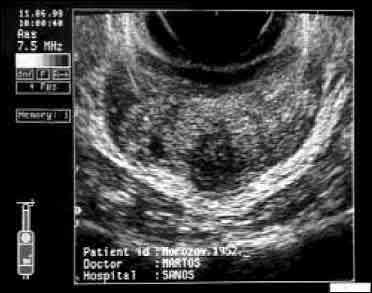

| ТРУЗИ простаты больного М., 1952 г.р. до лечения. Поперечное (а) и продольное (б) сканирование. Снижение эхогенности ткани в области верхушки железы и в виде радиальных полос от вентральной поверхности к центру железы - результат пальцевого массажа. Определяется периуретральный и паравезикальный отек. | |